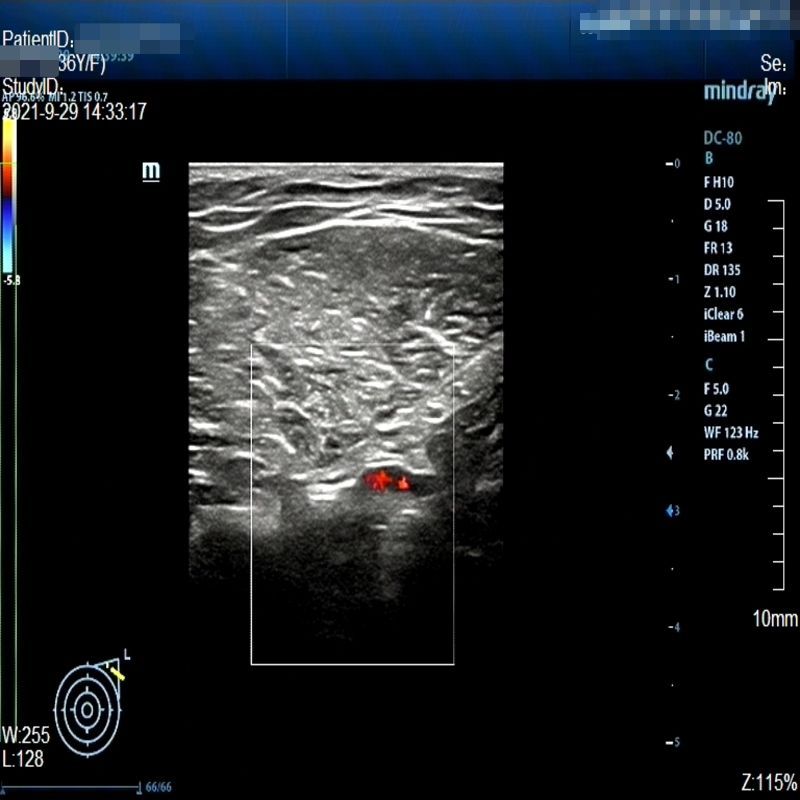

Images with certain annotations are considered noisy images in the context of the noise removal task, and corresponding images without these annotations are considered clean. Some typical images with various annotation are provided in Fig. 1.

(a)

(b)

(c)

Figure 1: Images with various annotations. (a) body marker annotation, (b) radical line annotation, (c) vascular flow annotation.